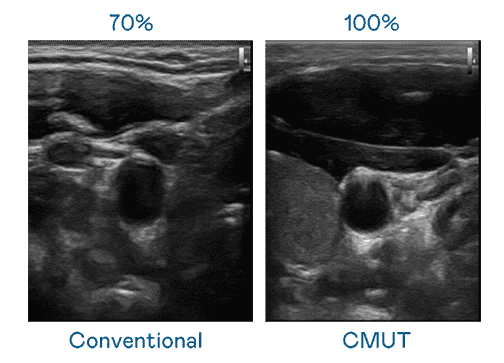

CMUT 技术是一种用电容式微机电元件来产生超音波讯号的技术。。与传统 PZT 压电式技术相比,,CMUT 频宽增加 30%,,,更宽频的超音波讯号让影像解析度大幅提升,,是实现高影像品质医疗超音波扫描、、促进精准医疗发展的关键技术。。。

超音波影像的解析度高低,,首先取决于探头能发出的讯号频宽。。z6尊龙 CMUT 可提供高清晰的超音波讯号,,提供高频宽、、、、高灵敏度、、、影像纹理细节更高的超音波影像,,,协助医护人员缩短影像判读时间及利用精准的医疗影像进行诊断。。